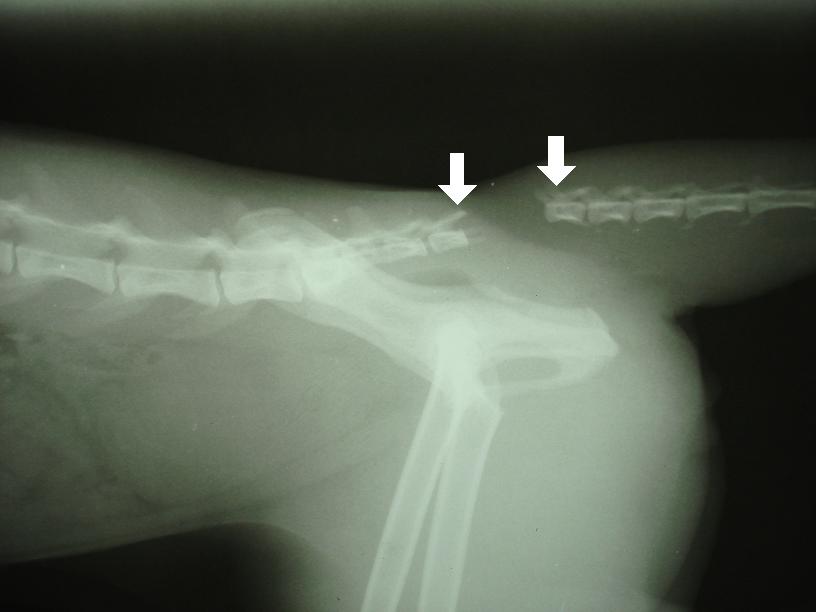

Na následujících snímcích je vidět zásadní oddálení (dislokace) 1. a 2. ocasního obratle (šipky). Došlo tedy k „odtržení“ ocasu, respektive ocasních obratlů počínaje 2. ocasním obratlem od zbylé části páteře.

Kosti pánve, zadních končetin, křížové kosti a bederních obratlů jsou rentgenologicky neporušené.